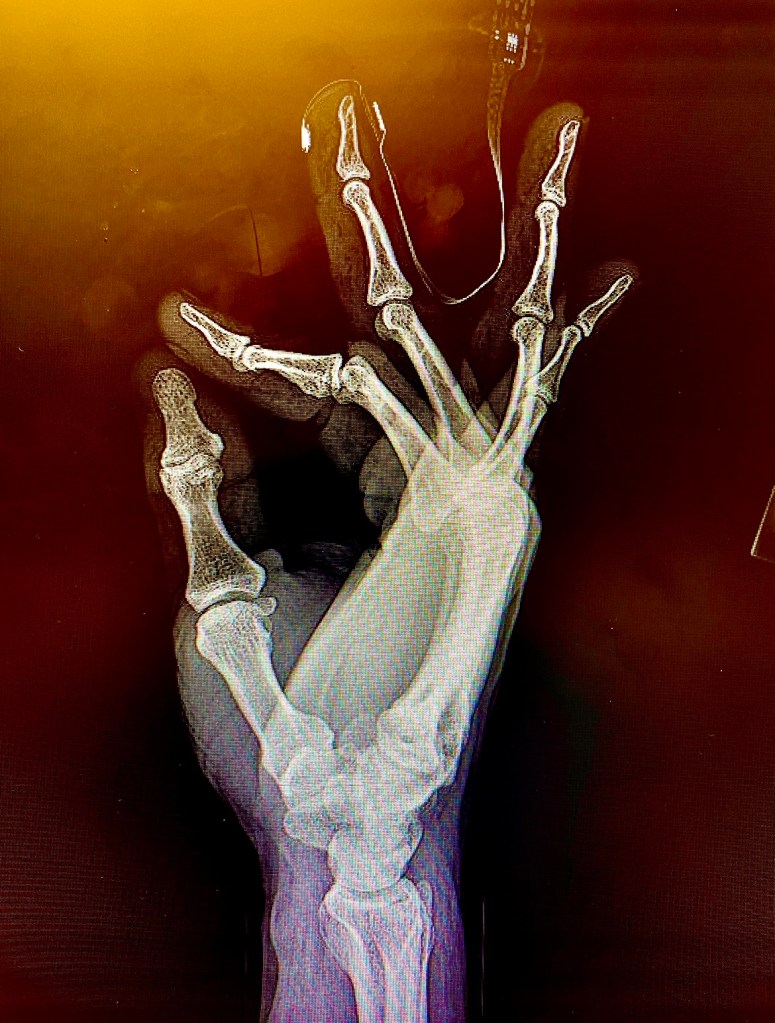

I was then rolled into the hallway and taken for a battery of scans, X-ray’s and tests. My knee which took the worst of it was very swollen and the pain felt like it was about to pop. Anytime they moved the gurney, the pain would intensify to a point that was unbearable.